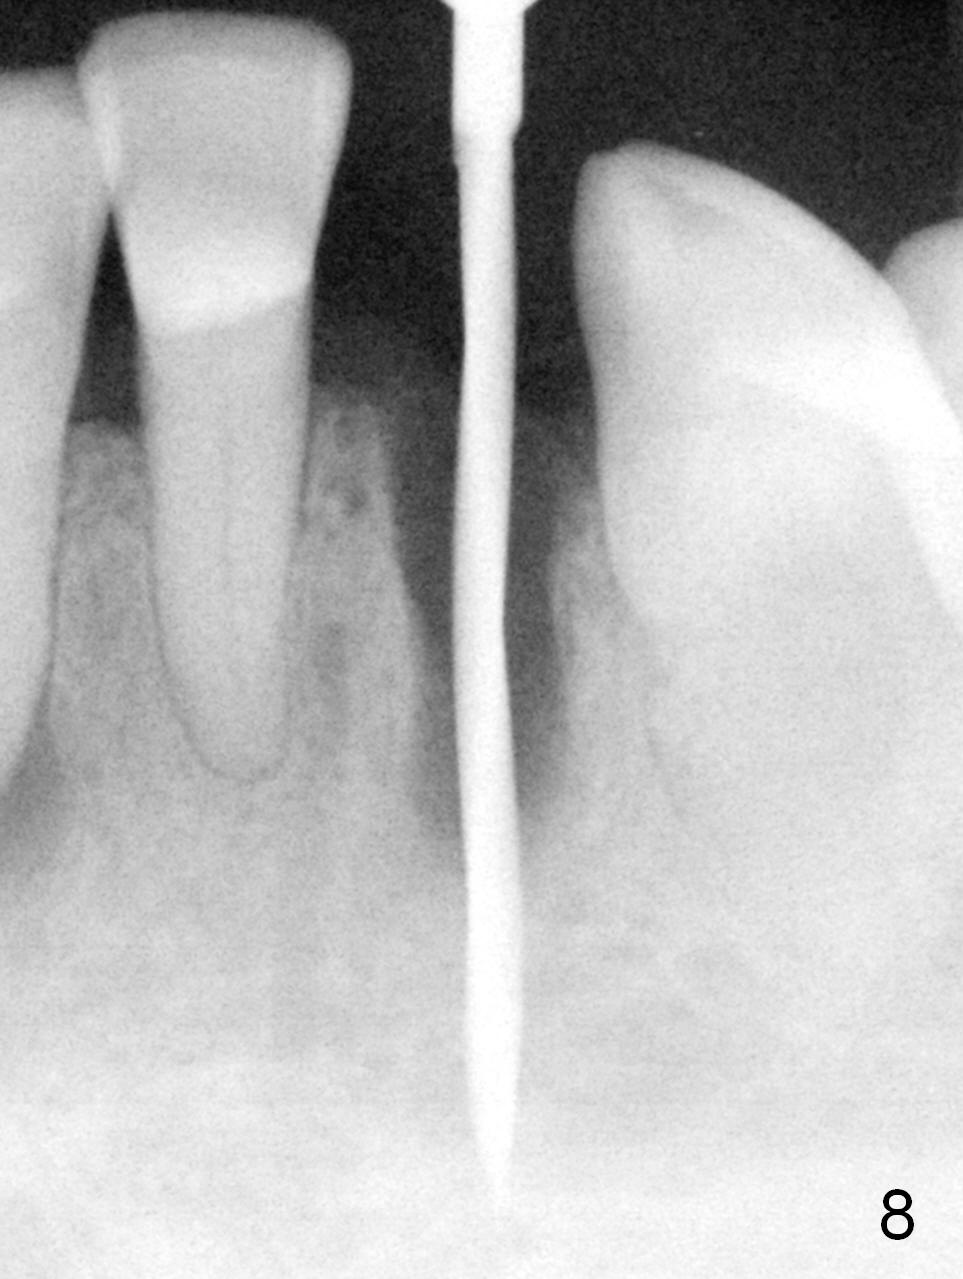

A 74-year-old man has several missing teeth (Fig.1).  His 1st goal is to replace the lower left lateral incisor (Fig.2).  The residual root has an apical lesion (Fig.3 *).  To describe intraop findings, a CT image of a different patient is used (Fig.4 coronal section; B: buccal; L: lingual).  After extraction, the buccal plate is found to be thin and low (Fig.5 arrowheads).  A 1.5 mm pilot drill (Fig.6 red line) is used to initiate osteotomy in the lingual plate of the socket.  Once the drill penetrates the lingual plate, the trajectory changes and the depth is 17 mm from the gingival margin (Fig.7).  A PA is taken (Fig.8); it appears that the osteotomy can be extended more apically.  When the pilot drill extends to 20 mm, there is sudden empty feeling.  The lingual plate has perforated (Fig.9).  A new osteotomy is established buccally (Fig.10 pink).  To avoid buccal plate perforation, especially in the buccal undercut area (>), the coronal end of the drill has to be tilted buccally (<--).  An angled abutment (3x20 mm, 15°) is placed (Fig.11,12).  The abutment is modified (Fig.13,14) to accommodate an immediate provisional (Fig.15,16 P).  Perio dressing is to be applied to prevent the bone graft from getting dislodged buccally (Fig.15).  The dressing is in place 7 days postop (Fig.17).